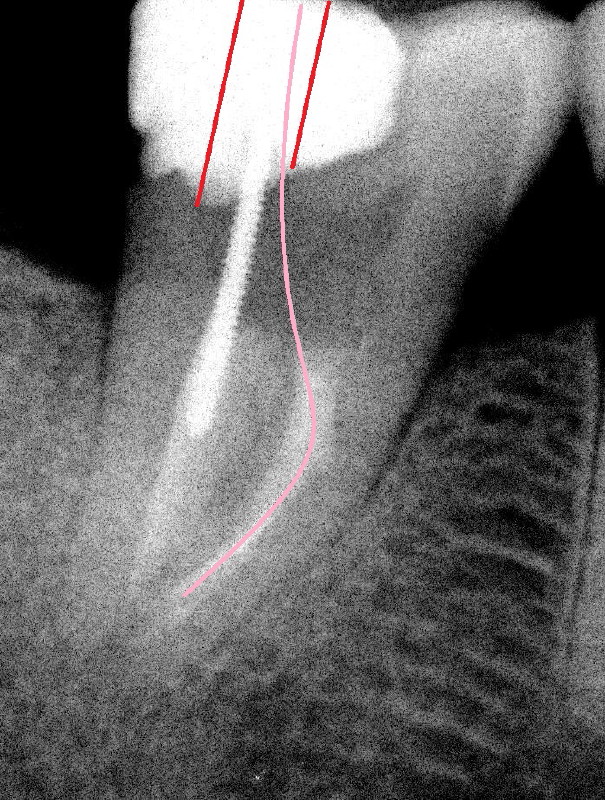

In fact, there is a separated file in the mesial canal (Fig.2: S). The related problem is that the mesial portion of the pulpal roof is not removed (arrowheads). The access to the pulp is limited (Fig.3: red lines), particularly to the mesial canal. The file must have been bent twice (pink line in an S shape) before separation. By comparison, the access to the pulp of another lower 2nd molar is sufficient (Fig.4 red lines) and the file is bent only once (pink line).